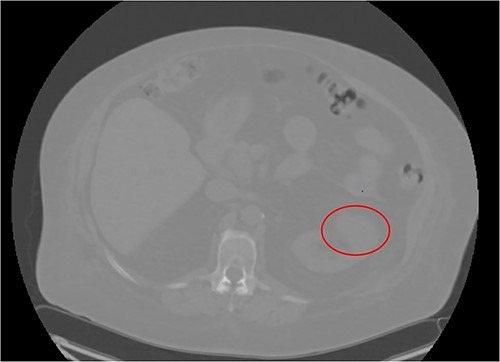

A 66-year-old morbidly obese female with relevant past medical history of type 2 diabetes mellitus, hypertension, and end stage renal disease on peritoneal dialysis (PD) was found to have an incidental enhancing right renal mass concerning for neoplasm on computerized tomography (CT) urogram workup for bacterial peritonitis secondary to streptococcus agalactiae bacteremia (Figs 1 and 2). After appropriate antibiotic treatment and discharge, the patient followed up in clinic where review of the incidental exophytic 16 mm renal mass confirmed suspicions for renal cell carcinoma. The patient still produced urine and was on the transplant list, but wished to proceed with RAPN of the suspicious lesion. A decision was made to use the patient’s PD catheter given her preoperative score of >3 on the Hostile Abdomen Index [5]. In addition to history of bacterial peritonitis, the patient had a notable past surgical history of open cholecystectomy, umbilical hernia repair, and laparoscopic peritoneal dialysis catheter placement in the past 3 months. She was also awaiting a transplant donor, and wished to remain on the list. In the operative theater, her double-cuffed Tenckhoff PD catheter was capped and prepped into the sterile field. Insufflation tubing was connected to the PD catheter and pneumoperitoneum was achieved with normal opening pressure. Laparoscopic trocars were sequentially placed and RAPN was completed without complication. The patient’s post-operative course was unremarkable. Upon physical examination at her 1 month follow-up, her incision sites remained clean, dry, and intact with no complaints of pain. She denied dysuria and gross hematuria. She was cleared to restart peritoneal dialysis at that time. Subsequent pathologic examination of the renal mass confirmed Type 2 Renal Cell Carcinoma with pathologic stage classification T1a, N0 and no signs of regional lymph node metastasis. The patient was instructed to follow-up in 6 months but was ultimately lost to follow-up on our urologic service.

CT Urogram demonstrating right renal mass suspicious for neoplasm.